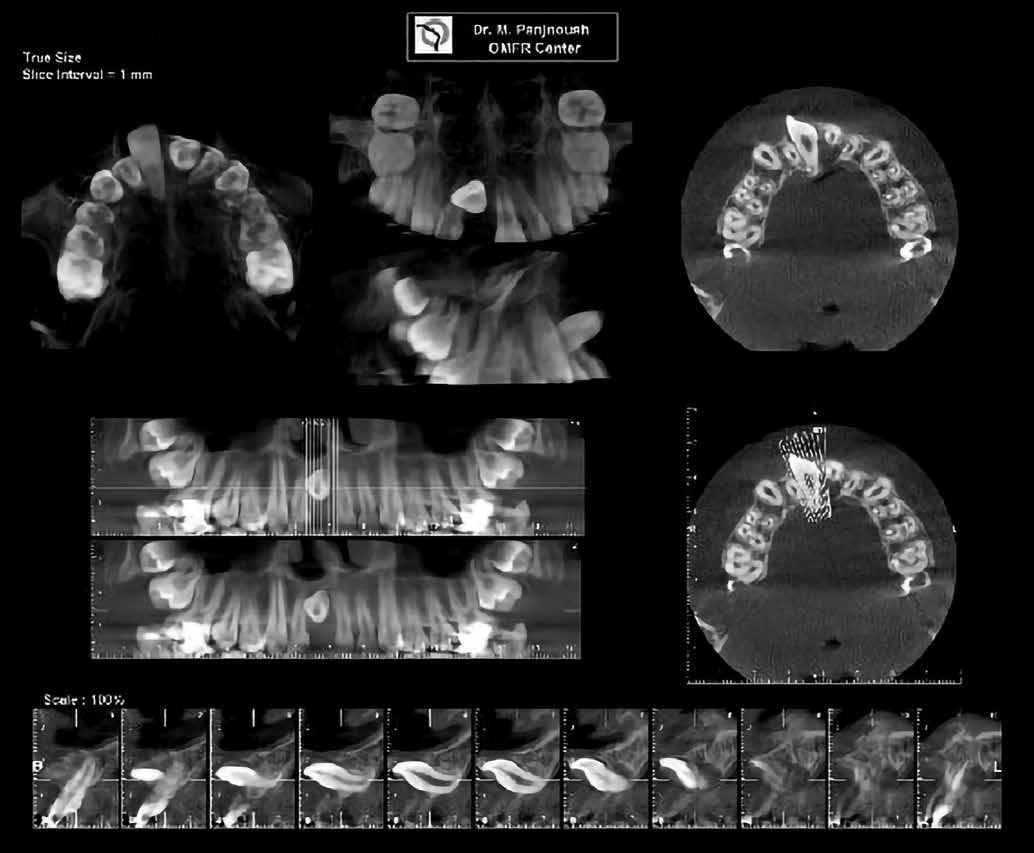

1. b ábra: A panoráma röntgenfelvételen megfigyelhető a teljes impakcióban lévő jobb felső nagymetszőfog. 1. c ábra: A CBCT felvétel is igazolja a jobb felső nagymetszőfog impakcióját.

4. a ábra: A CBCT felvétel igazolja, hogy a jobb felső nagymetszőfog megfelelő pozícióba került. Az ínyszél lefutása kedvező, a fog gyökere körül elfogadható mennyiségű csontállomány ábrázolódik, valamint a gyökérfelszívódás mértéke sem túl kifejezett.

A kezelés befejezésekor a páciens mosolya drámai mértékben javult, továbbá a frontfogak elhelyezkedése és az ínyszél lefutása is szemmel látható módon kedvezőbbé vált (4. ábra). A kezelés végén készült CBCT felvétel nem mutatta

csontfelszívódás jelenlétét, és csupán minimális mértékű gyökérfelszívódás bekövetkezését igazolta.

4. b ábra: A panoráma röntgenfelvétel is alátámasztja a CBCT felvételen látottakat. 4. c ábra: Az intraorális felvételen megfelelő fogpozíciók és kedvező ínyszéli lefutás ábrázolódik.